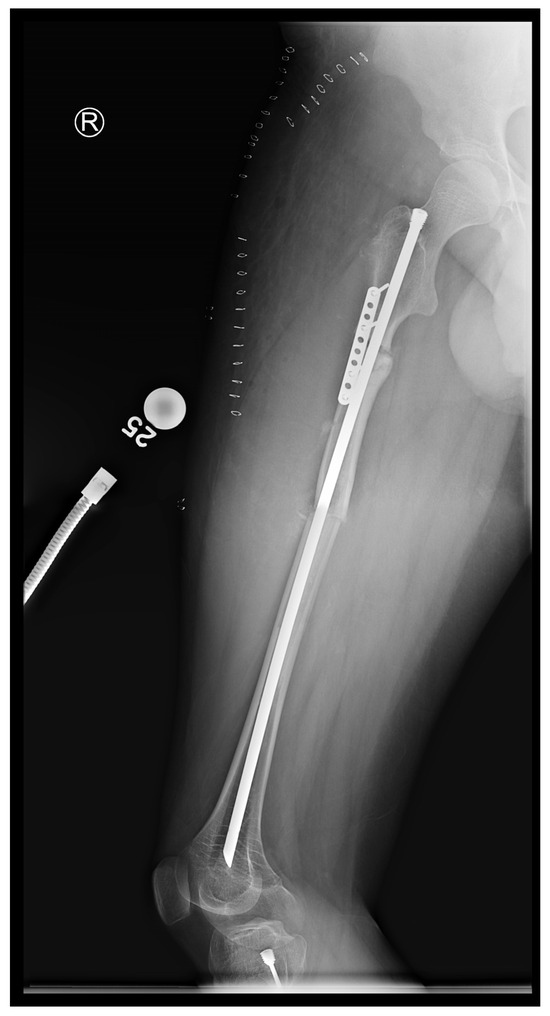

In the third case, a 16-year-old skeletally mature patient with OI was scheduled to undergo revision from FD rod to SLIM nail after presenting with pain due to stress fractures and wild deformity in his proximal right femur (Figure 11). The FD rod was removed, and then, using a piriformis entry point, access to the femur and proximal reaming was performed. There were two CORAs; the first CORA was identified in the subtrochanteric region, and a percutaneous osteotomy technique was performed to realign the bone, and then reaming was continued (Figure 12). The second CORA was identified, and another percutaneous osteotomy was performed, and the bone was cracked with a closed osteoclasis technique, and then reaming was continued in the distal segment (Figure 13). The SLIM nail was then inserted and had an excellent fit. The subtrochanteric region was under high stress, so a 2.7 Smith and Nephew EVOS plate to further stabilize the segment and control the rotation. Two screws were placed above and below (Figure 14). In this case, the indication for the use of the SLIM nail was the need to revise the existing telescoping FD rod in a skeletally mature patient to a solid nail. As the intramedullary canal was too small to accommodate a larger solid nail, a SLIM nail was used instead. The use of a plate as an adjunct to an intramedullary nail is also shown.

Figure 14.

Post-operative X-ray showing SLIM nail and plate.